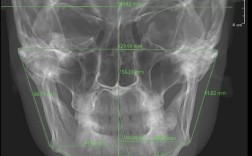

(图片来源网络,侵删)- 硅橡胶类: 最常用,包括: